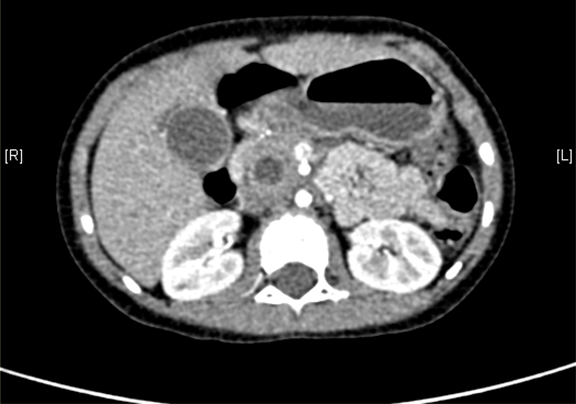

术前CT检查:

动脉期

上腹部增强CT:1. 胆总管囊肿、肝内胆管略扩张2. 胆囊壁厚,考虑胆囊炎可能性大。